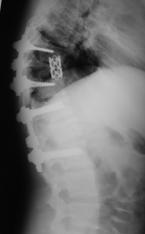

При малых сроках от момента травмы (от нескольких часов до 2-5 дней) операцию выполняли в объеме задней непрямой репозиции и стабилизации многоопорной металлоконструкцией с опорой на интактные тела позвонков в сочетании с задним локальным спондилодезом. При взрывном переломе тела одного позвонка осуществляли транспедикулярную фиксацию в пределах двух смежных позвоночно-двигательных сегментов с опорой на соседние интактные позвонки, непрямую репозицию тела сломанного позвонка. Завершали операцию формированием заднего локального спондилодеза вдоль металлоконструкции (рис. 10).

Рис. 10. Рентгенограммы пациента К. 16 лет. Взрывной перелом L1

А – КТ до операции; Б – после задней непрямой репозиции, транспедикулярной фиксации и заднего спондилодеза |